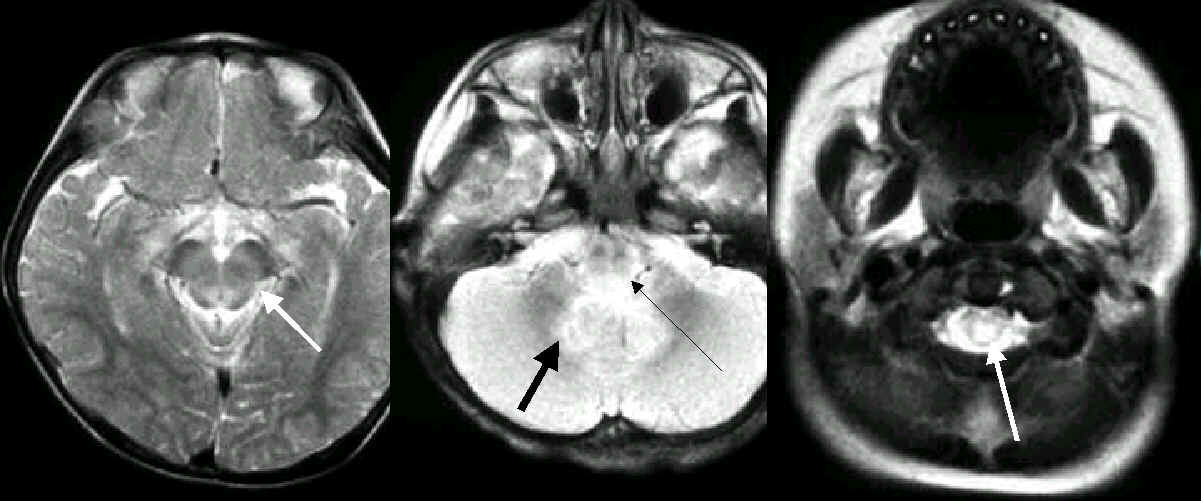

本院自今年五月至今門診已診療過一千六百多例腸病毒引起手足口

疾病,20人有腦炎跡象,其中12人病況嚴重住入小兒加護病房。這些病

患7人做了MRI,前四人中只有一例在腦幹的橋腦後面有一點不正常訊號

,我們不敢確認是否有意義?但最近的三人,則都可明確地看到在中腦正

中央,橋腦後面,以及小腦齒狀核有明確的不正常訊號,其中一人延腦

後方也有,最嚴重的一例除了上述腦幹位置及小腦齒狀核之外,更往下

侵犯到頸椎的脊髓。MRI所發現的這些腦炎侵犯腦幹的證據,與臨床症狀

相吻合,也就是嗜睡、呼吸困難、血壓下降,而小腦的侵犯也可以解釋

雙手顫抖、步態不穩(一例四歲男孩)。

七例中有三例這麼明顯的發現,因此可以做一個初步的結論:

MRI 的影像顯示腸病毒引發的腦炎是侵犯

腦幹之中腦、橋腦的後方

以及小腦的齒狀核

嚴重者往下侵犯到

延腦的後方

甚至到頸椎的脊髓

4/y boy, hand-foot-mouth disease associated with encephalitis, caused

by enterovirus 71

|

Hyperintensity lesions in the midbrain, the cortico-spinal tractsare spared.

Hyperintensity lesionsin the posterior aspect of pons, and the bilateral dentate nuclei of cerebellum.

2/y girl, hand-foot-mouth disease associated with encephalitis, caused by

enterovirus 71

Hyperintensity lesions

in the midbrain, the

cortico-spinal tractsare

spared.

in the posterior aspect

of pons,and the bilateral

dentate nuclei of

cerebellum.

The cervicalspinal

cord is also involved.

2/y girl, hand-foot-mouth disease associated with encephalitis, caused by enterovirus 71

Hyperintensity lesions in the posterior aspect of pons & medulla

oblongata, and the bilateral dentate nuclei of cerebellum, and downward to the cervical

spinal cord.